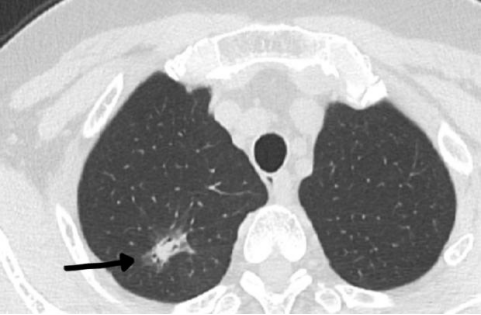

患者张女士(化名)在门诊CT检查时,发现右肺上叶占位性病变。经详细讨论并与患者及家属充分沟通后,决定实施肺结节活检穿刺术。

术前,鉴于患者病灶实性成分少,被磨玻璃成分环绕,介入放射科团队在周巍主任的带领下,通过CT精准引导,成功将一根细针经皮肤穿刺至肺结节实性部位,取出活检组织进行病理检查。整个手术过程顺利,患者术中无明显不适,术后也未出现严重并发症。术后病理结果提示为腺癌,为后续抗肿瘤治疗方案的制定提供了关键依据。